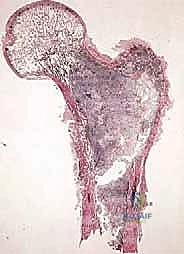

1. ساركوما العظام (Bone Sarcomas)

تنشأ في العظام نفسها وتصيب غالباً الأطفال والشباب. من أشهر أنواعها:

* الساركوما العظمية (Osteosarcoma): الأكثر شيوعاً، تظهر عادة حول الركبة (أسفل الفخذ أو أعلى القصبة).

تتميز هذه الأورام بقدرتها على اختراق الأنسجة المجاورة وتكوين ما يُعرف بـ "المنطقة التفاعلية" (Reactive Zone) أو الكبسولة الكاذبة، والتي تحتوي غالباً على خلايا سرطانية مجهرية. هذا المفهوم البيولوجي هو ما يوجه الدكتور محمد هطيف في تحديد مدى الاستئصال الجراحي.